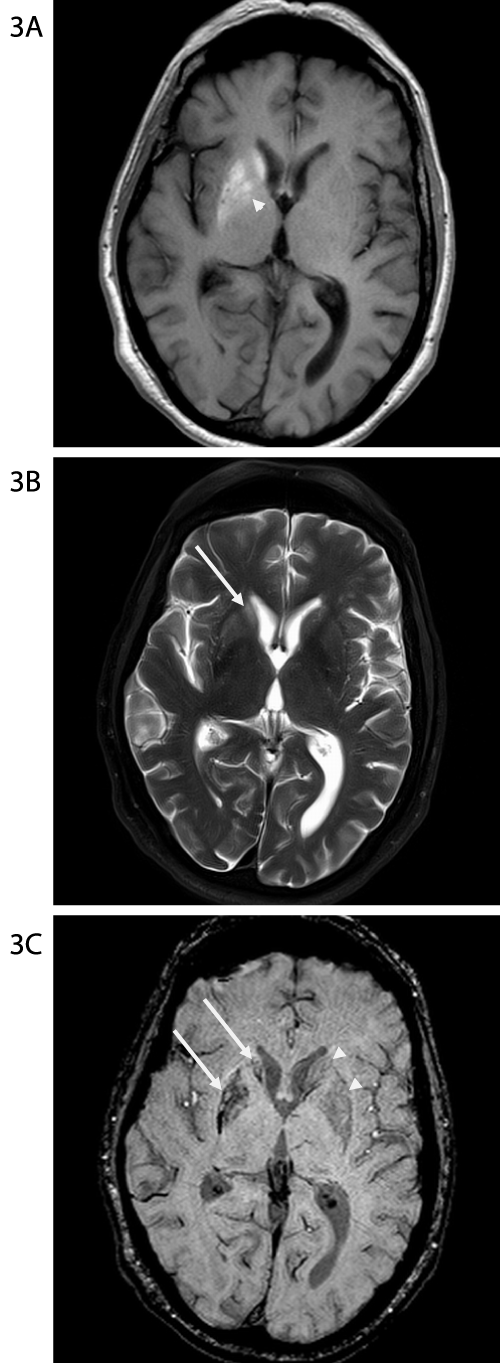

Figure 3A-C: MR scan obtained 5 weeks after the scans in Figures 1 &

2. On the axial non-contrast T1-weighted image at the level of the basal

ganglia (Figure 3A) there is now greater hyperintensity in the globus pallidus

(arrowhead), but there is otherwise similar hyperintensity within the right

caudate head and lentiform nucleus. On the T2-weighted image (Figure 3B),

the extent of hyperintensity within the right lentiform nucleus is reasonably

similar to the appearance on the prior study, however there is now greater

hyperintensity in the right caudate nucleus head (long arrow). On the

susceptibility weighted image (Figure 3C), the extent of the susceptibility

artifact is also not significantly changed. Note that the right basal ganglia (long

arrows) are smaller than the left (arrowheads).

He had already failed a trial of muscle relaxants and benzodiazepines. Haloperidol provided no benefit. A combination of benztropine and clonazepam seemed to help but led to gait and cognitive impairment. With tetrabenazine the movements became intermittent and less intense. Eight months after the onset there was significant improvement but not complete resolution. Repeat MRI 5 weeks later showed greater hyperintensity in the globus pallidus on the axial, non-contrast T1-weighted image but otherwise similar hyperintensity within the right caudate head and putamen. On the T2-weighted image, the hyperintensity within the right lentiform nucleus was similar to that seen on the prior study; however there was greater hyperintensity in the head of the right caudate nucleus. The right basal ganglia appeared smaller than the left.

Radiological findings were also characteristic in this case. There was complete sparing of internal capsule, thus pointing towards a metabolic rather than a vascular insult [8,9]. While there was gradual evolution of changes on imaging, there was persistence of T2 hyperintensity in the right lentiform nucleus. Follow-up MRI also showed unilateral atrophy of basal ganglia. Basal ganglia atrophy resulting in hyperkinetic movements is a known feature of various hereditary neurodegenerative disorders, but it is rarely reported in HCHB. A few patients with persistent HCHB due to non-ketotic hyperglycemia were noted to have basal ganglia lacunae. Surprisingly our patient developed unilateral basal ganglia atrophy in the absence of evident ischemic infarcts.